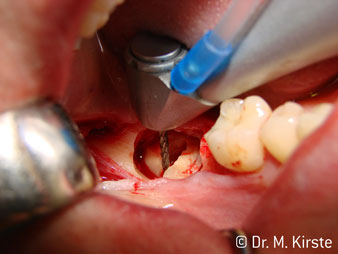

Elegir el ángulo de 45º ofrece múltiples ventajas de uso. Los odontólogos dedicados a cirugía (para quienes se desarrolló principalmente esta pieza de mano) se percatarán de inmediato de que se puede trabajar de forma muy específica. En especial en la remoción de las muelas del juicio (Fig. 2), no es necesaria una gran abducción de las partes blandas en la zona del carrillo (Fig. 3). El diseño del cabezal de la pieza de mano, combinado con los suaves giros del cabezal durante la preparación, permite trabajar de forma rápida y segura en la zona retromolar.

El nuevo diseño de los rodamientos dentro del cabezal de la pieza de mano garantiza el funcionamiento silencioso de la fresa, en la separación del diente o la raíz (Fig. 4-9) se muestra una impresionante imagen de corte sin efectos de impacto.

El contra-ángulo de 45º se adapta muy bien a la mano. Es fácil darse cuenta de que el cabezal de trabajo sigue el ángulo del dedo índice y, así, el movimiento deseado solo se desplaza unos centímetros en paralelo a la punta (Fig. 1)."